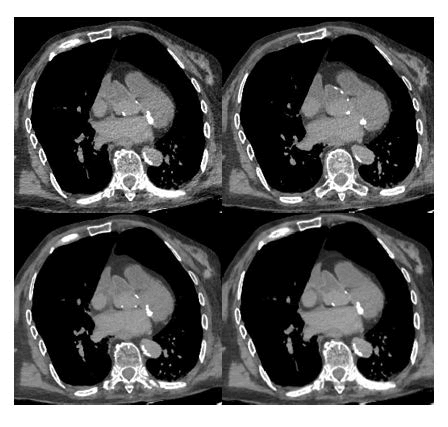

What we have observed for pediatric virtuopsy is also valid for adults.

Take, for example, Figure 9, where the same image from four different acquisition sets is compared. In this case, three CT scans of the chest were performed on an 82-year-old deceased individual. The scanning parameters were kept the same for all three packages, except for the different kilovoltage values: 80 KV, 100 KV and 120 KV. Finally, a fused CT reconstruction was performed by summing the raw data from all the acquisitions.

As observed previously, there is a decrease in the absolute value of noise with increasing KV values, resulting in improved spatial resolution and clarity in identifying the boundaries of various structures. However, visually, there is a perceived flattening due to the decrease in contrast resolution.

Focusing on the origin of the ascending aorta, we can see how the issues identified with the other datasets are mitigated with the fusion CT technique: The vessel profile becomes sharp and well-defined, the contrast between the vessel lumen and surrounding tissues is enhanced and the noise is drastically reduced.

XXXXXXXX

Figure 9. Comparison of images of the mediastinum with fusion CT and acquisitions at different energies: Respectively 80 KV (top left), 100 KV (top right), 120 KV (bottom left) and fusion CT reconstruction of the previous (bottom right).